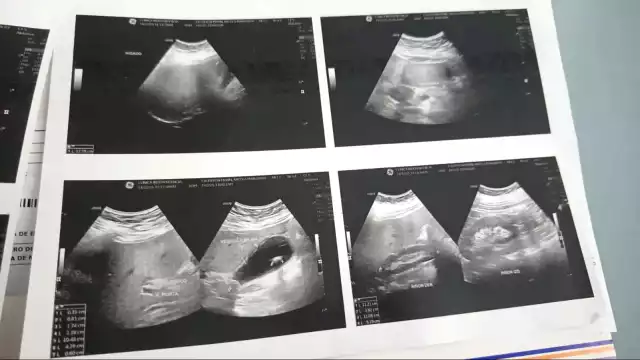

Debido a esta omisión, la paciente tuvo que ser trasladada a una clínica privada para someterse al estudio médico, cuyo costo fue cubierto por sus familiares. Los resultados revelaron la presencia de cálculos en la vesícula, uno de los cuales la obstruye, provocando una lesión que podría derivar en una infección grave si no se atiende oportunamente. No obstante, en el ISSSTE aún no se le han practicado los análisis necesarios para confirmar dicha complicación.